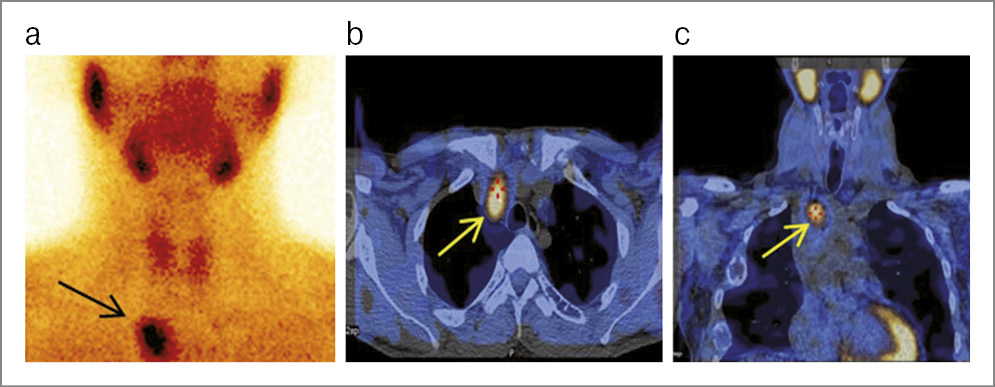

ПЭТ/КТ с 18F-холином проведена 10 пациентам в возрасте от 53 до 69 лет, медиана – 60,5 года. На I этапе выполнены УЗИ и ОФЭКТ/КТ с целью определения локализации аденом околощитовидных желез. При этом у 2 больных после сцинтиграфии получен сомнительный, а в 2 случаях – отрицательный результат. После ПЭТ/КТ с 18F-холином во всех случаях выявлены аденомы околощитовидных желез различной локализации, включая эктопические варианты – в стенке шейного отдела пищевода и в заднем средостении (рис. 2).

Рис. 2. Пациентка А., 59 лет. На MIP ПЭТ/КТ, аксиальных и корональных КТ- и ПЭТ/КТ-срезах с 18F-холином кзади от левой доли щитовидной железы, у стенки шейного отдела пищевода (уровень СVII) визуализируется метаболически активный очаг размерами 8×8×16 мм, SUVmax 6,0. Аналогичное образование на уровне ТhI–ТhIII справа, распространяется пара/ретротрахеально в заднее средостение размерами до 29×15×47 мм, SUVmax 10,6. Заключение: аденомы эктопированных паращитовидных желез в стенке шейного отдела пищевода слева и в заднем средостении справа.

Для разграничения аденом околощитовидных желез от ткани щитовидной железы F. Dekorsy и соавт. (2022 г.) определили уровень стандартизированного коэффициента максимального накопления (SUVmax), который, по их данным, составил 4,36 [16].

По нашим данным, в холинозависимых поражениях средняя величина SUVmax составила 5,43 (диапазон 3,2–10,6), а средний размер образований – 9,8×18,9 мм (диапазон 8×11 – 15×47 мм).

В нашем исследовании с помощью гибридной технологии ПЭТ/КТ с 18F-холином во всех случаях получен положительный результат по идентификации аденом околощитовидных желез.

Данный факт свидетельствует о том, что этот метод позволяет определить их локализацию и метаболическую активность при отрицательных и сомнительных случаях, полученных при различных методах визуализации.